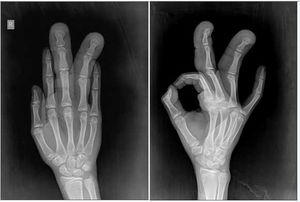

MacrodactylyByPratiksha Yadav, MDNovember 15th 2013Case History: A 12-year-old girl presented with history of enlargement of middle and ring fingers of right hand since birth.